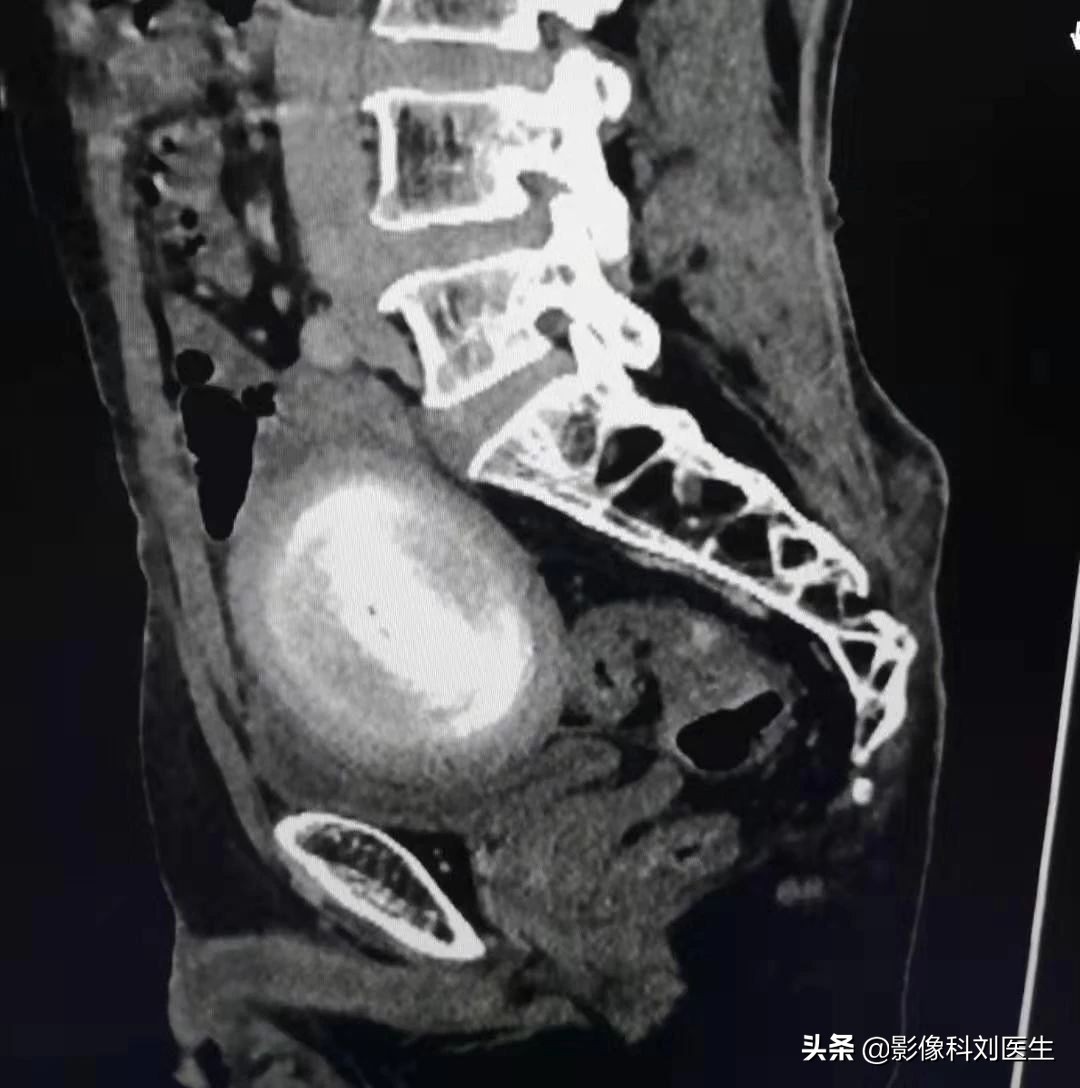

CT矢状位

今年88岁的李大爷,虽然年龄比较大了,但身体一向比较好,平时也经常锻炼、很少住院,而就在最近,李大爷逐渐的出现了腹部疼痛,刚开始的时候,疼痛比较轻,呈隐痛,大爷以为是自己吃了什么不卫生的东西,也就没太在意,认为忍一忍就过去了。但是一周过去了,疼痛不但没有减轻,反而越发的严重了,李大爷感觉到了不对劲,赶紧来到了医院进行检查。来到医院后,接诊的外科医生发现大爷精神较差,下腹部压痛明显、腹胀,于是立即开了CT检查来我科检查,而CT检查一做,我们意外发现,李大爷的盆腔内见大小约9.5x6.5cm的高密度肿块,边缘光滑,犹如“鸭蛋”大小。与周围结构分界尚清除。由于平时我们也很少遇到类似病例,所以一时也无法定性诊断,不过观察比邻关系,应该可以进行手术治疗,于是便马上连续了外科医生,希望能得到他术后的病理诊断,从而进行学习补充。

外科医生在经过详细的病情评估后,发现李大爷的病变有手术指征,同时李大爷是完全可以承受手术治疗的,于是便立即进行了腹部的手术治疗,而手术中发现:盆腔内有一游离、光滑、实性、坚硬的包块,大小约10x8x6.6cm。手术顺利取出了鸭蛋大小的包块,而术后,李大爷也恢复的很快,腹部疼痛症状以及其他症状都基本消失了,病理也提示是一个纤维样的良性病变,不需要进行进一步的治疗。李大爷在经过几天的术后治疗后,也顺利出院回家了。